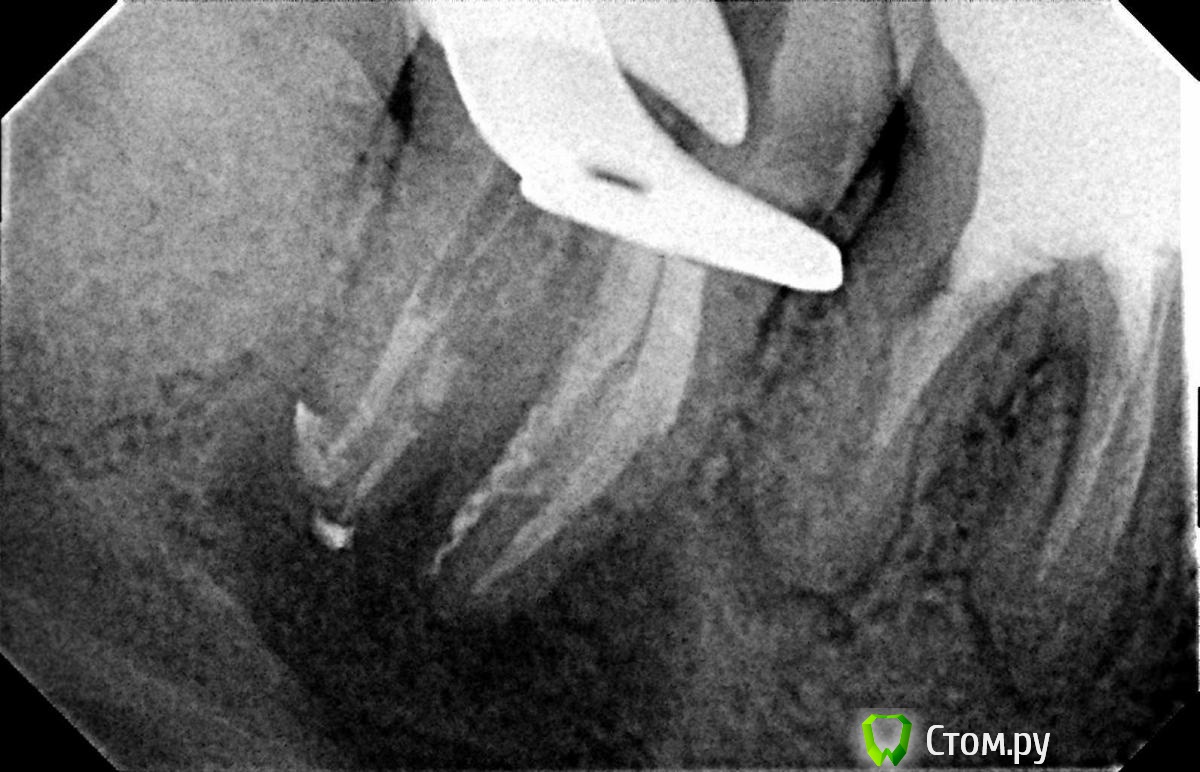

Л Ю С Я Опубликовано 10 января, 2014 Поделиться Опубликовано 10 января, 2014 .Новый кейс-совсем свежий пока без долгосрочного результата.Пациентка попала случайно удаляла зуб 28 и хирург сделал ОПТГ,где стали видны обширные периапикальные процессы в области 37 47.Побывав у меня на консультации и услышав план лечения и стоимость,пациентка решила видимо полечить подешевле.,побывав на консультациях в нескольких клиниках и в итоге даже попала к главному стоматологу нашей области. Все ей сказали что удаление онли. Вернулась,-засада была в том что план я писал исходя из ОТПГ не сделав прицел(виноват),сделав прицел понимаю что все сложнее чем я думал-ну что же тем интереснее.Переписав план лечения и подняв ценник на 40%(пациентке не оставалась выбора),начали лечение.1-посещение-ревизия пломбы.понимаю что кто то до меня с маниакальным упорством пытался запломбировать мезиальный язычный канал каналонаполнителями. Убрал два фрагмента из верхней трети мезиального язычного.2-посещение еще фрагмент из мез язычного плюс немного с дистальными поработал(их оказалось два сплит в верхней трети)3-визит обошел фрагмент в мезиальном щечном и доработал остальные каналы.4-визит -паковка.На предпоследнем снимке видны поры-допаковал(просто на финальном не очень видно)Класс! Ждем рекол через 6 месяцев. Паковка чем? Сквирт? Ссылка на комментарий